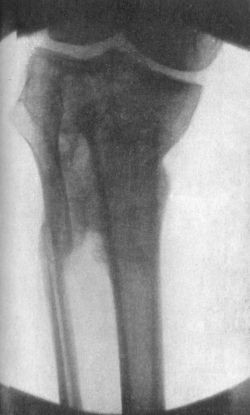

161 84.Radiogram of Fracture of Head of Tibia and upper Third of Fibula

163 85.Radiogram illustrating Schlatter's Disease